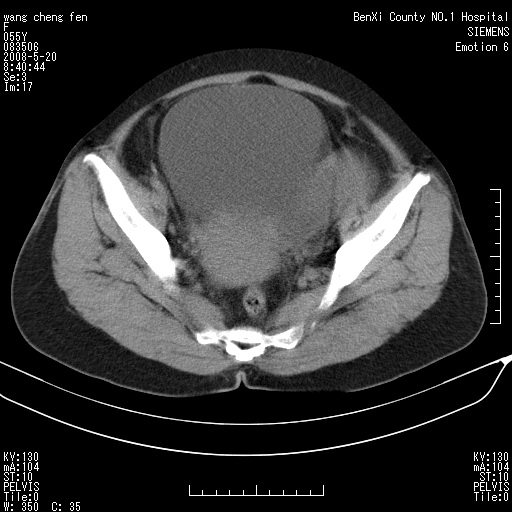

女、绝经后阴道流血3个月

左侧附件区巨大囊实性病灶,边缘光整,病灶囊壁较厚,增强示囊壁及实性部分明显强化,强化呈度与宫体实质大致相同,宫腔积液征像,未见盆腔积液等其他异常,考虑左侧卵巢囊腺癌,不除外囊腺瘤及浆膜下肌瘤坏死

左侧附件区巨大囊实性病灶,边缘光整,病灶囊壁较厚,增强示囊壁及实性部分明显强化,强化呈度与宫体实质大致相同,宫腔积液征像,未见盆腔积液等其他异常。绝经后阴道流血3个月,结合病史左侧卵巢囊腺癌首先考虑,宫腔扩大不除外累及。期待结果。

左侧卵巢囊实性占位,结合年龄和病史,考虑卵巢囊腺癌或囊腺瘤。

缺延时片子,左侧盆腔囊实性占位,来自于左侧附件可能性大,囊腺癌可能性大。

囊实性肿块分隔厚度较大,厚薄不均,增强实性成分明显强化,有不规则阴道流血,卵巢囊腺癌可能性大。